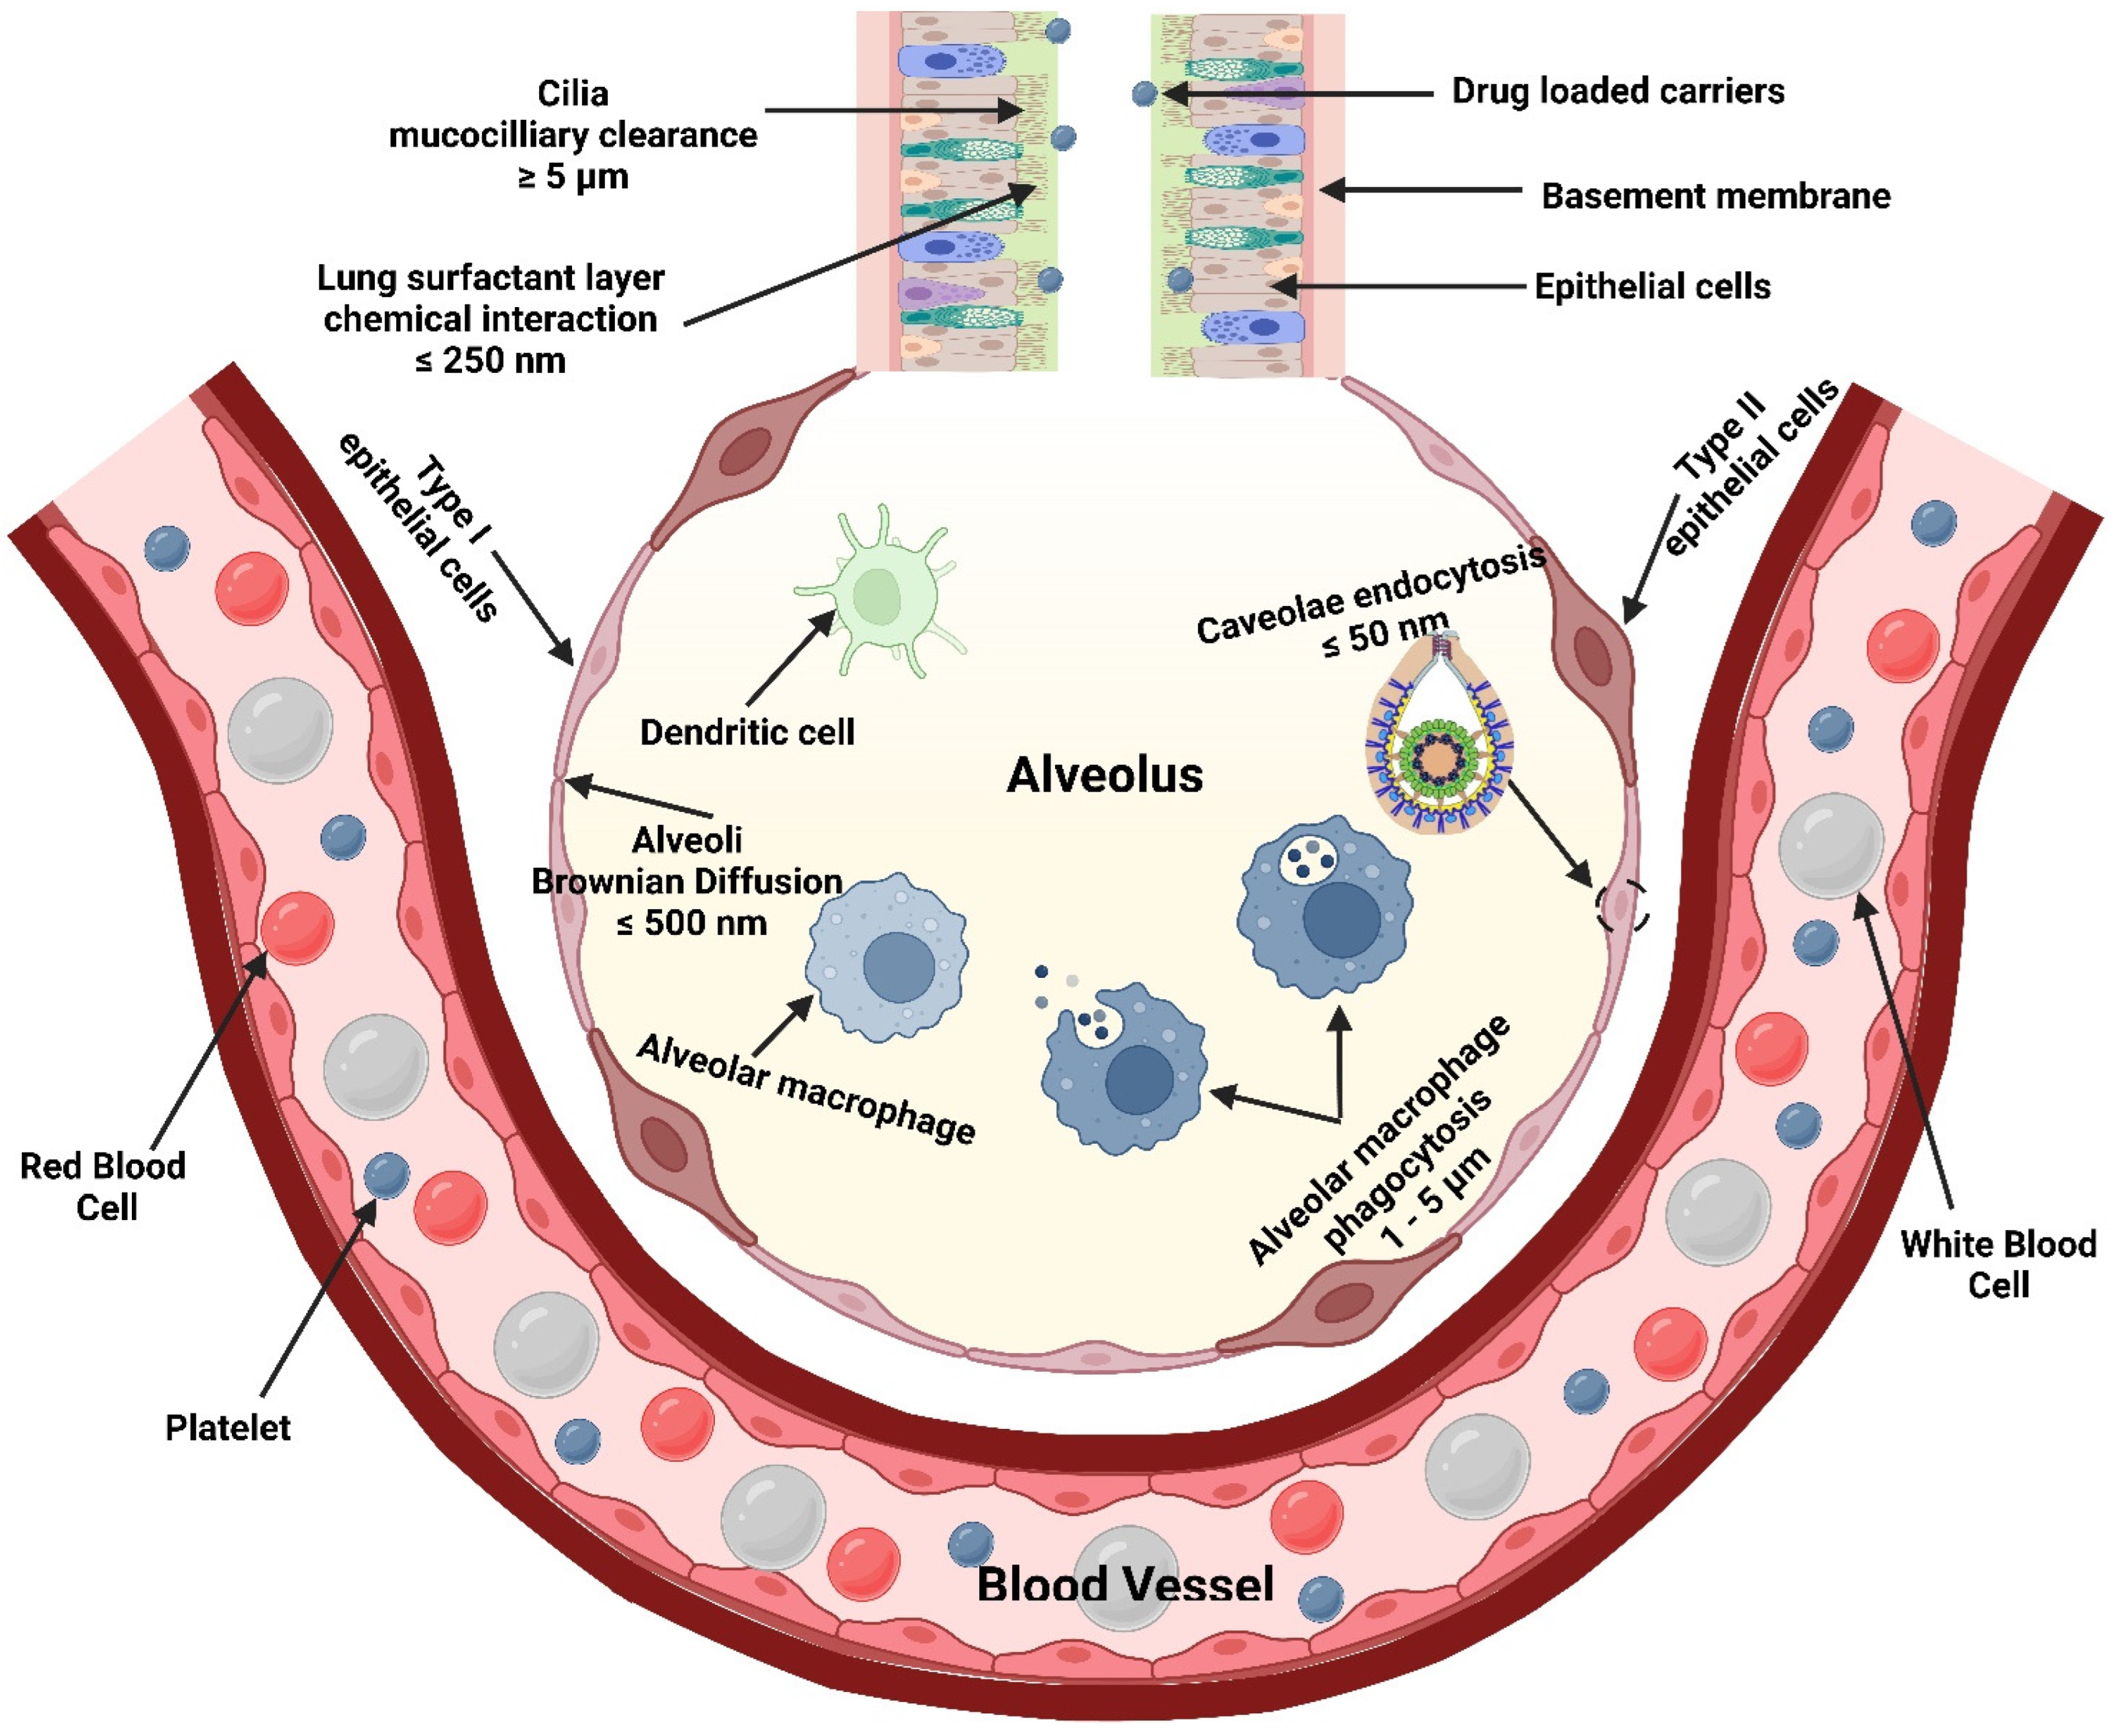

Particle Size and Deposition Pattern

Particle Surface Charge

- Murgia, X.; de Souza Carvalho, C.; Lehr, C.-M. Overcoming the pulmonary barrier: New insights to improve the efficiency of inhaled therapeutics. Eur. J. Nanomed. 2014, 6, 157–169. [Google Scholar] [CrossRef]

- Darquenne, C. Deposition mechanisms. J. Aerosol Med. Pulm. Drug Deliv. 2020, 33, 181–185. [Google Scholar] [CrossRef]

- Hofmann, W. Modelling inhaled particle deposition in the human lung—A review. J Aerosol Sci. 2011, 42, 693–724. [Google Scholar] [CrossRef]

- Patel, B.; Gupta, N.; Ahsan, F. Particle engineering to enhance or lessen particle uptake by alveolar macrophages and to influence the therapeutic outcome. Eur. J. Pharm. Biopharm. 2015, 89, 163–174. [Google Scholar] [CrossRef]